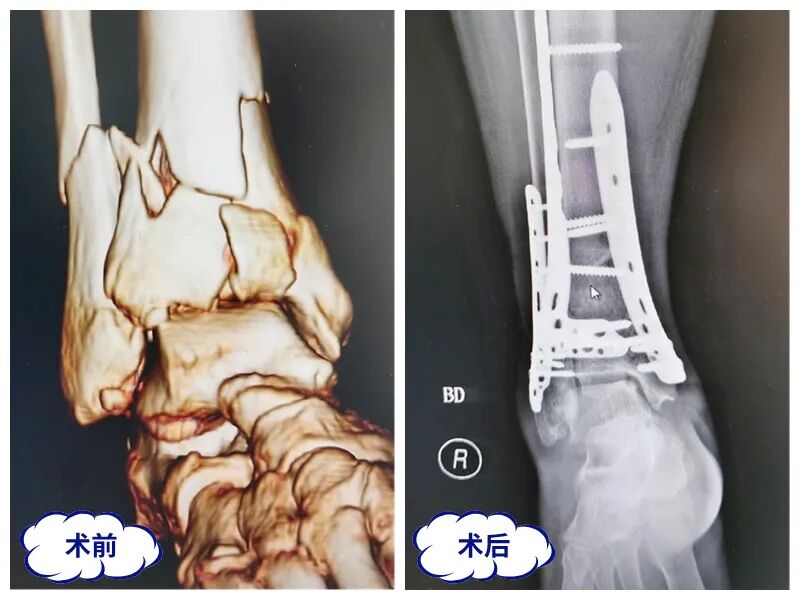

创伤专业